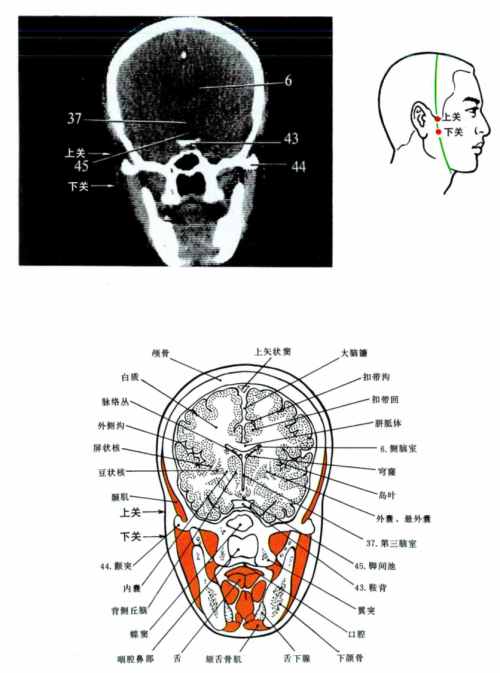

2.3. Rapports et coupes anatomiques

- Deng 1993 : Peau—tissu sous-cutané—glande parotide—entre le muscle masséter et l'apophyse zygomatique de l'os temporal—muscle ptérygoïdien externe. Dans la couche superficielle, on trouve les branches du nerf auriculo-temporal, les branches zygomatiques du nerf facial, et l'artère et la veine transverses faciales. Dans la couche profonde, on trouve l'artère et la veine maxillaires, le nerf lingual, le nerf alvéolaire, l'artère méningée moyenne et le plexus ptérygoïdien.